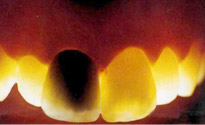

ポーセレンラミネートべニア

歯の表面を一層削った所に薄いポーセレンを貼りつけるやり方です。